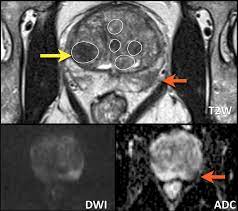

Prostate Cancer Diagnosis Radiology : The Diagnostic Value Of Pi Rads V1 And V2 Using Multiparametric Mri In Transition Zone Prostate Clinical Cancer - If you have been diagnosed with adenocarcinoma cancer, you have a cancer that developed in one of the glands that lines the inside of your organs.

Prostate Cancer Diagnosis Radiology : The Diagnostic Value Of Pi Rads V1 And V2 Using Multiparametric Mri In Transition Zone Prostate Clinical Cancer - If you have been diagnosed with adenocarcinoma cancer, you have a cancer that developed in one of the glands that lines the inside of your organs.. You will find a list of common tests, procedures, and scans that doctors use to find the cause of a medical problem. Use the menu to see other pages.doctors use many tests to find, or diagnose, cancer. Being armed with information is vital to begin the fight. Prostate cancer is one of the most common types of cancer diagnosed in men. However, as with other types of cancer,.